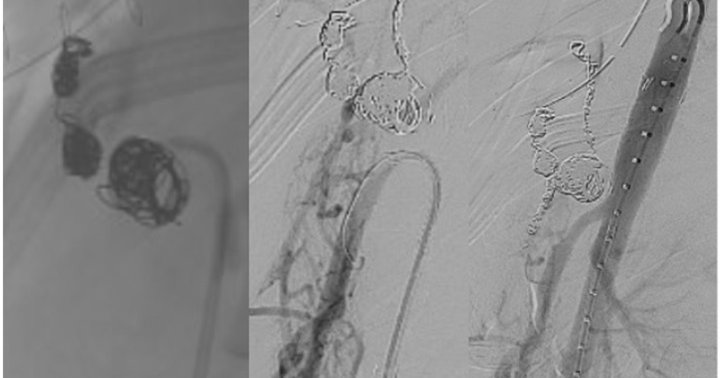

ππ©» When Type II endoleak gets complex. This case describes successful coil + Onyx embolization via a transcaval approach for a Type II endoleak with aortocaval fistula after EVAR using balloon occlusion & co-axial microcatheter. π https://t.co/xKAqTlVst0

#EVAR #Endoleak

jvscit.org

Endovascular aortic repair is an accepted treatment option for patients with infrarenal aortic aneurysm. Type II endoleak associated with persistent aneurysmal sac growth is considered an adverse...